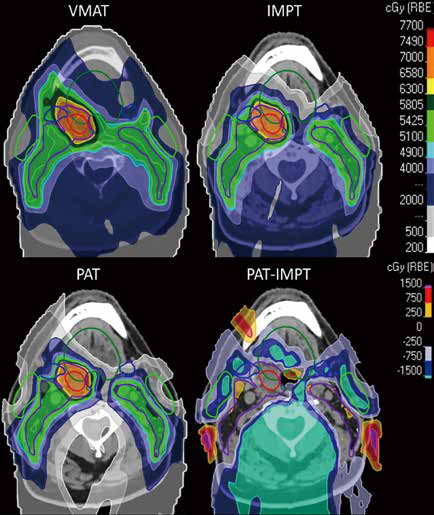

为了描述根治性放疗的OPSCC患者中ORN的发生率、严重程度及预测因素,并比较质子放疗与IMRT的结局,该项回顾性队列研究连续纳入了2013年1月至2023年12月在单个大接诊量学术机构接受IMRT或质子放疗的OPSCC患者。ORN的诊断和分级通过标准化的多学科团队评审来确定。

任何级别ORN的3年发生率为3.02%(95%CI 2.22%~4.09%)。质子放疗组和IMRT组的3年ORN发生率分别为6.36%和2.69%(HR=2.62,95%CI 1.39~4.93)。在1344例根治性治疗的患者中,IMRT组(1210例)和质子放疗组(134例)的ORN事件分别有47例次和11例次,对应的3年ORN率分别为2.38%(95%CI 1.61%~3.51%)和7.47%(95%CI 3.40%~16.02%;HR=3.62,95%CI 1.85~7.09)。

多变量分析显示,质子放疗(HR=2.92,95%CI 1.55~5.50)、同步化疗(HR=3.29,95%CI 1.03~10.50)及吸烟(HR=2.33,95%CI 1.38~3.92)均与ORN独立相关。≥3级ORN发生率为0.67%,且在不同放疗方式间似乎无明显差异。 (编译 陈博)